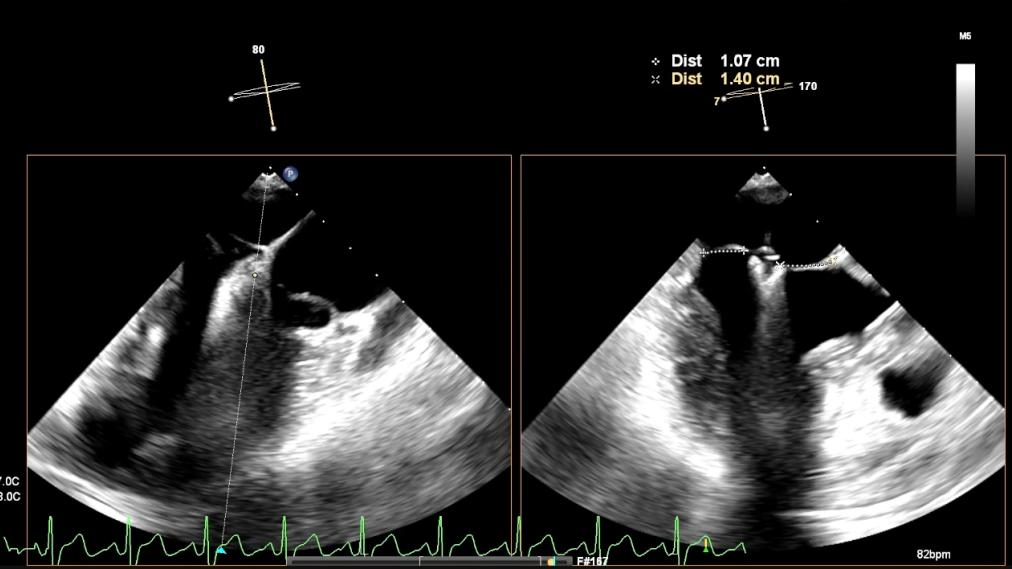

超声心动图(经胸超声心动图,TTE)示:

左心室射血分数(LVEF):75%,左心房前后径:38mm;

二尖瓣P2区大部分瓣叶在收缩期脱入左心房,断裂腱索残端摆动,呈连枷样运动;

连枷宽度:15mm,连枷间隙:6mm;

二尖瓣环AP径:33mm;

AL-PM径:35mm;

有效反流口面积(EROA):0.67cm²。

超声心动图诊断:

二尖瓣反流(退行性,CarpentierⅡ型,4+);

二尖瓣后叶脱垂伴腱索断裂。

术前超声影像

3D

3D彩

术前超声